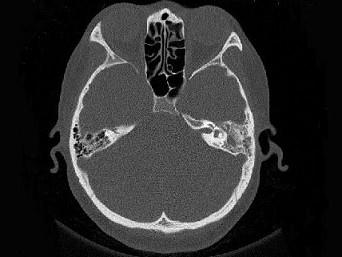

问题 女,34岁,左耳鸣,听力下降两个月,PE:左外耳道有脓性分泌物,鼓膜充血水肿,左中耳腔内软组织影,CT检查如图,最可能诊断为 ( )

选项 A、肉芽肿形成 B、中耳结核 C、中耳癌 D、胆脂瘤 E、乳突癌

答案 A